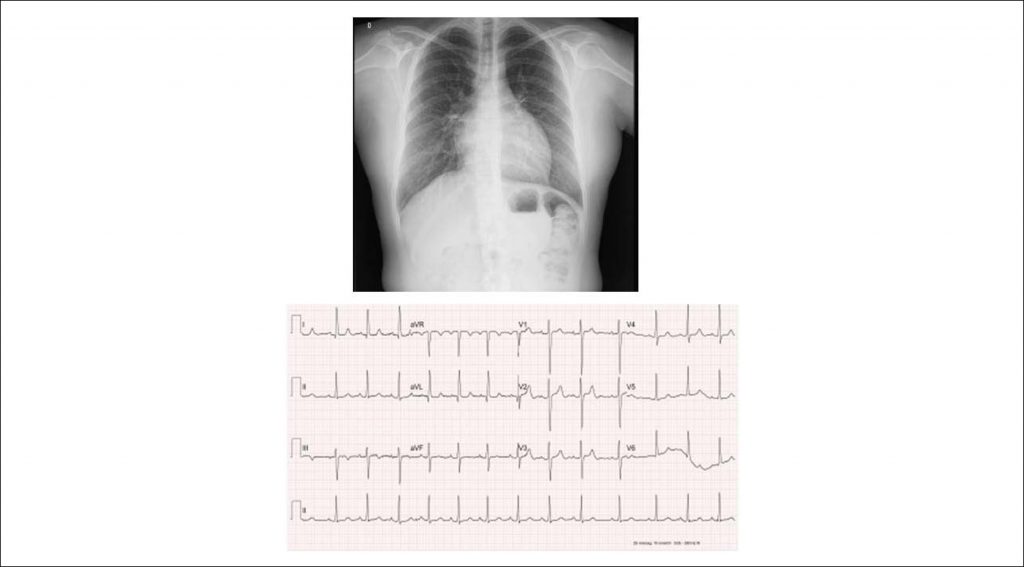

Case 2 / 2019 – Complete Atrioventricular Septal Defect, with Down Syndrome, without Pulmonary Hypertension and Natural History at 33 Years of Age

The patient has developed no symptoms since birth, when heart disease was diagnosed by the presence of heart murmur in the presence of physical elements of Down syndrome. The patient is currently able to walk approximately 30 minutes daily without showing signs of fatigue and accompanies other individuals normally. The patient uses enalapril and levothyroxine for hypothyroidism.

Physical examination: good overall status, eupneic, acyanotic, normal pulses in the 4 limbs. Weight: 41 kg, Height: 131 cm, MBP in the right upper limb: 110 x 60 mmHg, HR: 93 bpm, Sat O2: 97%.